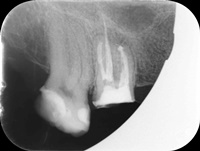

Pacjentka zgłosiła się z bólem. Ząb prawa dolna czwórka po leczeniu kanałowym. Nawracające dolegliwości bólowe, od kilku lat okresowo zaostrzające się. Podjęto decyzję o rewizji leczenia kanałowego. Udróżniono kanał korzeniowy, oraz odnaleziono kanał dodatkowy. Zdjęcie początkowe i zdjęcie po leczeniu endodontycznym pod mikroskopem.